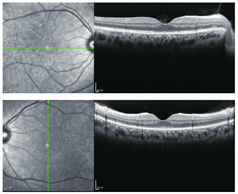

Gass随诊的病例中有39例双眼发病,占76%[2]。本例患者左眼发病间隔18d后右眼也出现了与左眼相同症状,双眼OCT显示IS/OS光带模糊不清(图2)。结合患者的症状和辅助检查结果,我们考虑该患者诊断为双眼AZOOR。

眼底照相:未见异常,FFA检查:显示视网膜血管及各象限视网膜未见异常荧光。mfERG:显示后极部反应平坦,中心30°视野检查:除上方区域外,其余区域视野缺损,OCT检查:IS/OS中心凹处光带缺如,其周围光带模糊不清。